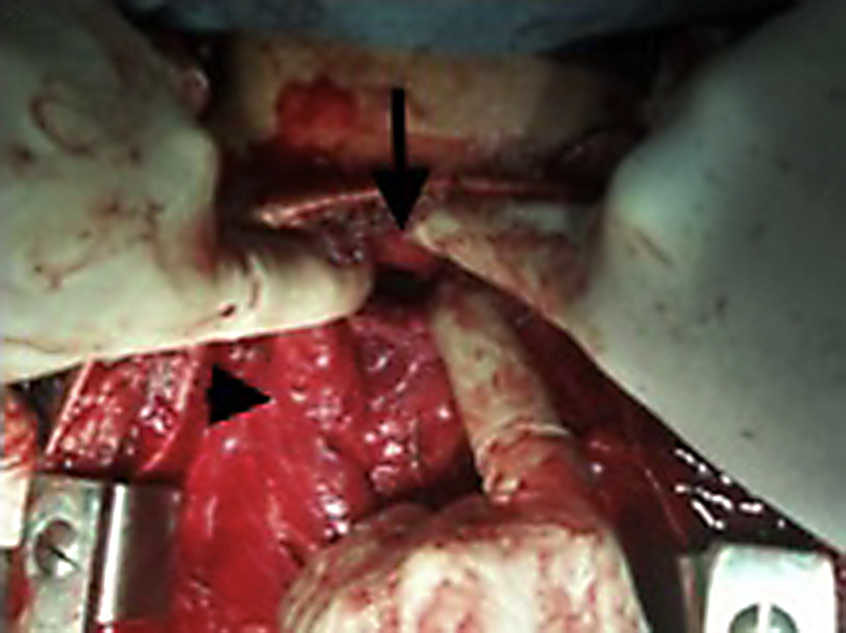

Se aborda la cavidad torácica a través de una esternotomía media. Se libera digitalmente el mediastino y se observa líquido lechoso abundante fluyendo en la cavidad pleural. Digitalmente se logra identificar el extremo proximal de la tráquea, el cual está ocupado por el tubo endotraqueal y el extremo de cánula fuera del cabo distal de la tráquea, por lo que se intuba digitalmente el extremo distal bajo visión directa (fig. 1).

Se realiza disección de vena innominada y tronco braquiocefálico. Se ubica el extremo del conducto torácico en el confluyente yugulosubclavio izquierdo el cual se ve evidencia seccionando y con flujo de linfa.

Se liga el conducto torácico con Vicryl®. Liberados los extremos proximal y distal de la tráquea se realiza rafia traqueal con sutura discontinua de Vicryl® 2/0 resecando fragmentos denudados de cartílagos traqueales, logrando bordes netos y que no exista fuga aérea (figs. 2–4).